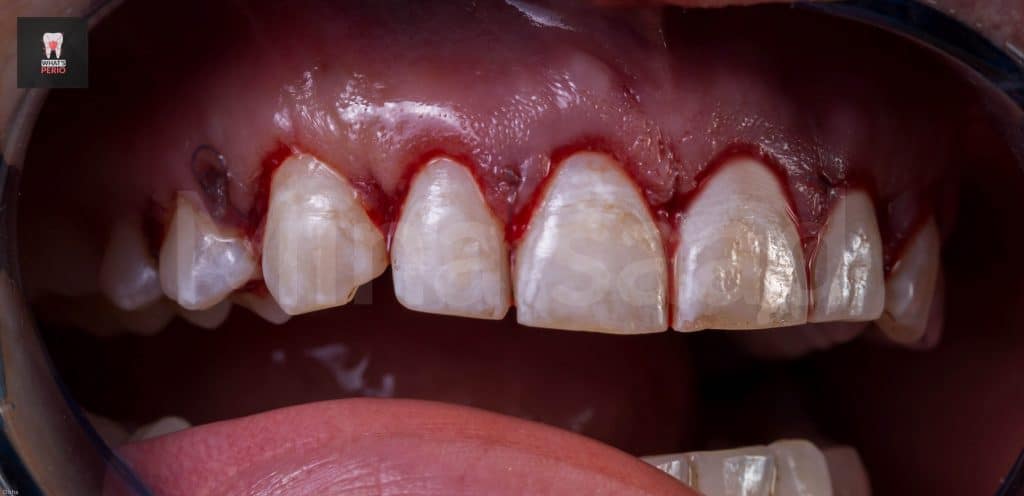

-Internal bevel incision was made “envelope flap” to expose underlying labial plate of bone.

-Care was taken during flap elevation to make a split-thickness incision under each papilla to preserve underlying periosteum interdentally as there is no need to expose interdental bone.

-The guide was placed again over labial plate of bone & it was noted that its apical level is higher than alveolar crest level.” Which confirms that the design on CBCT was accurate”

-Ostectomy was made using a rose head diamond stone then the guide was put in place again & it was observed that the apical level & the alveolar crest is at the same level now.

-Prominence of canine eminence of the right side was observed to more bulky than the left one . “this was confirmed clinically & radiographicaly in occlusal view of CBCT”

-Osteoplasty wass performed to reshape the prominent canine eminence to be in harmony with the left one & in general the labial plate of bone was shaped & any sharp angles resulting from ostectomy procedure were removed for better adaptation of the flap ensuring nice healing results.